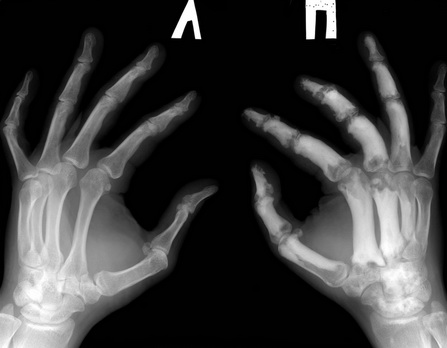

Уважаемые коллеги помогите. Для какого заболевания характерна такая R-картина

Обратился пациент на прием. Травмы не было. Болеет(со слов) в течении 10 лет, никогда и никуда не обращался, лечился сам чем мог. Анамнез не отягощенный. Последние 2 мес. отмечает значительное ухудшение, болит правая кисть, ни с чем не связывает. Более подробно напишу клинику и лабораторные показатели при явке пациента после дообследования

Похоже на Paget's Disease.

Посмотрите уровень щелочной фосфатазы в крови, уровень кальция, фосфора (обычно в норме). Можно сделать Тс сканирование, что бы определить другие

возможные участки измененного скелета.

Абсолютно согласен, что это мелореостоз. Лечение чисто симптоматическое, т.е. антивоспалительные обезболивающие. Сделайте поиск на интернете про мелореостоз и вы увидите аналогичные рентгены. Лучше всего, сделайте поиск на английском на "melorheostosis."